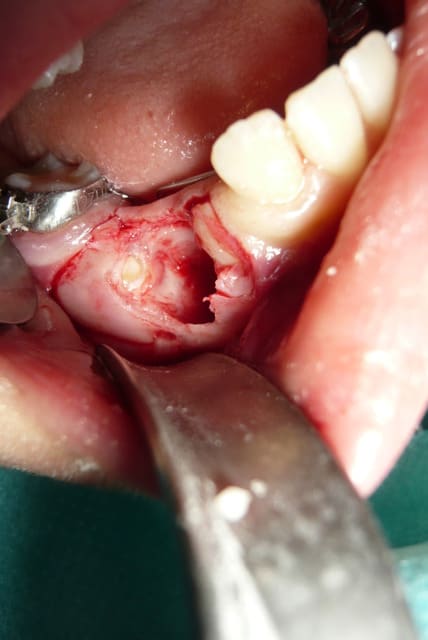

-lambeau vestibulaire à décharge trapézoîdale, à distance du foramen mentonier.

-décollement individualisation du foramen et protection lors de l'écartement

-morcellement simple de la dent et extraction..

-cone beam réalisé avant l'acte permettant de visualiser le foramen situé ici entre germe de 4 et 5 donc inévitable lors de la chirurgie.

- choix d'un lambeau avec décharges et à distance du foramen permettant de l'individualiser avec un décollement prudent. Puis protection idéalement par un écarteur non compressif :

séparation dentaire de la partie haute de la couronne permettant un dégagement osseux moindre, ainsi restant à distance de 2mm du foramen..

(foramen et pédicule mentonnier visible sur la photo avec l'extraction ).